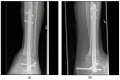

Joint destruction necessitates tibiotalocalcaneal arthrodesis (TTCA) in cases of clinical deficits that cannot be controlled conservatively, possibly leading to sepsis. We aimed to compare the underlying etiology of posttraumatic joint destruction and the outcomes after TTCA in patients with a septic or aseptic history. Between 2010 and 2022, 216 patients with TTCA were retrospectively enrolled (septic TTCA (S-TTCA) = 129; aseptic TTCA (A-TTCA) = 87). Patient demographics, etiology, Olerud and Molander Ankle Scores (OMASs), Foot Function Index (FFI-D) scores, and Short Form-12 Questionnaire (SF-12) scores were recorded. The mean follow-up period was 6.5 years. Tibial plafond and ankle fractures were the most common causes of sepsis. The mean OMAS was 43.0; the mean FFI-D was 76.7; and the mean SF-12 physical component summary score was 35.5. All the scores differed significantly between the groups (p < 0.001). With an average of 11 operations until the arthrodesis was achieved, the S-TTCA patients underwent about three times as many operations as the A-TTCA patients (p < 0.001), and 41% of S-TTCA patients remained permanently unable to work (p < 0.001). The significantly worse results of S-TTCA compared to A-TTCA show the long and stressful ordeal that patients with a septic history suffer. Further attention must be paid to infection prophylaxis and, if necessary, early infection revision.